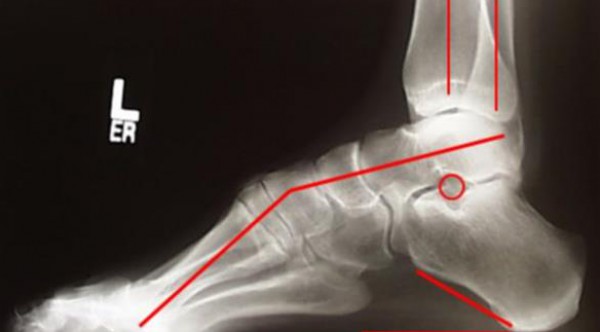

اكتشاف متلازمة الحبل المربوط

وأدت التجربة إلى اكتشاف كورتني متلازمة الحبل المربوط، ومن ثم حددت موعدا مع جراح أعصاب ليؤكد لها أن لدى أليكس حبلا شوكيا مربوطاً، وهو عيب خلقى يسبب مشكلت فى النمو، وغالباً لا يتم اكتشافه إلا فى مرحلة متأخرة.